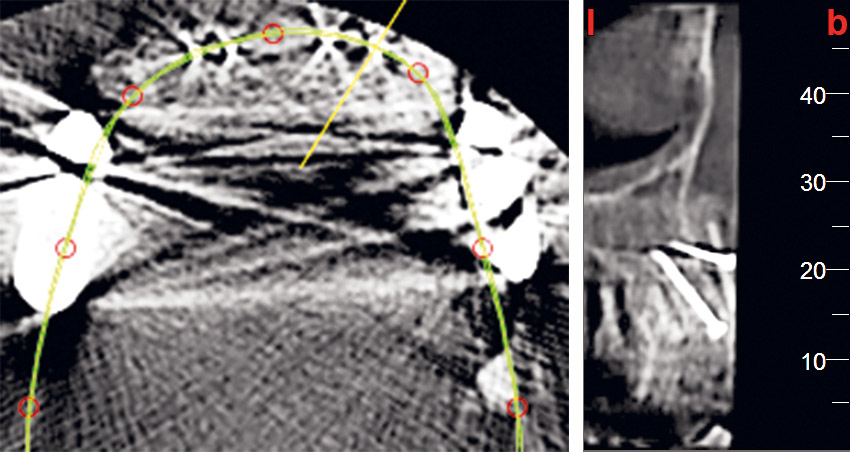

03 / 22 - Initial situation – CBCT image of the first quadrant

Three-dimensional augmentation with maxgraft® cortico - M.Sc. E. Kapogianni

04 / 22 - Initial situation – CBCT image of the second quadrant